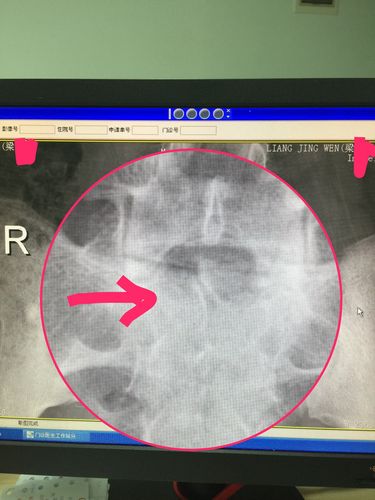

箭头指向的是骶骨隐裂,正常的应该有棘突果然,l5/s1椎间盘突出通过

骶椎隐裂加浮棘

Ⅲ度骶椎隐裂

Ⅱ度骶椎隐裂